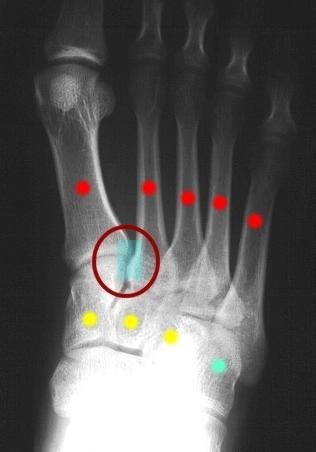

Figure 1: Normal AP xray of right foot. The yellow dots are the cuneiform bones (3). The red dots are the metatarsals (5). The teal dot is the cuboid bone. The red circle represents tthe Lisfranc joint between the 1st and 2nd metatarsals and the medial cuneiform bone.

The bones consist of the 3 cuneiform bones and the cuboid bone. Further towards the toes, are the metatarsal bones. Everywhere that these bones come together, there is a joint. The proper alignment of the bones at the joints is due to the ligaments that hold the bones in the proper place. The Lisfranc joint actually refers to a number of joints which are formed by the junction of the metatarsals and the cuneiforms, and by the junction of the metatarsals and the cuboid bone.